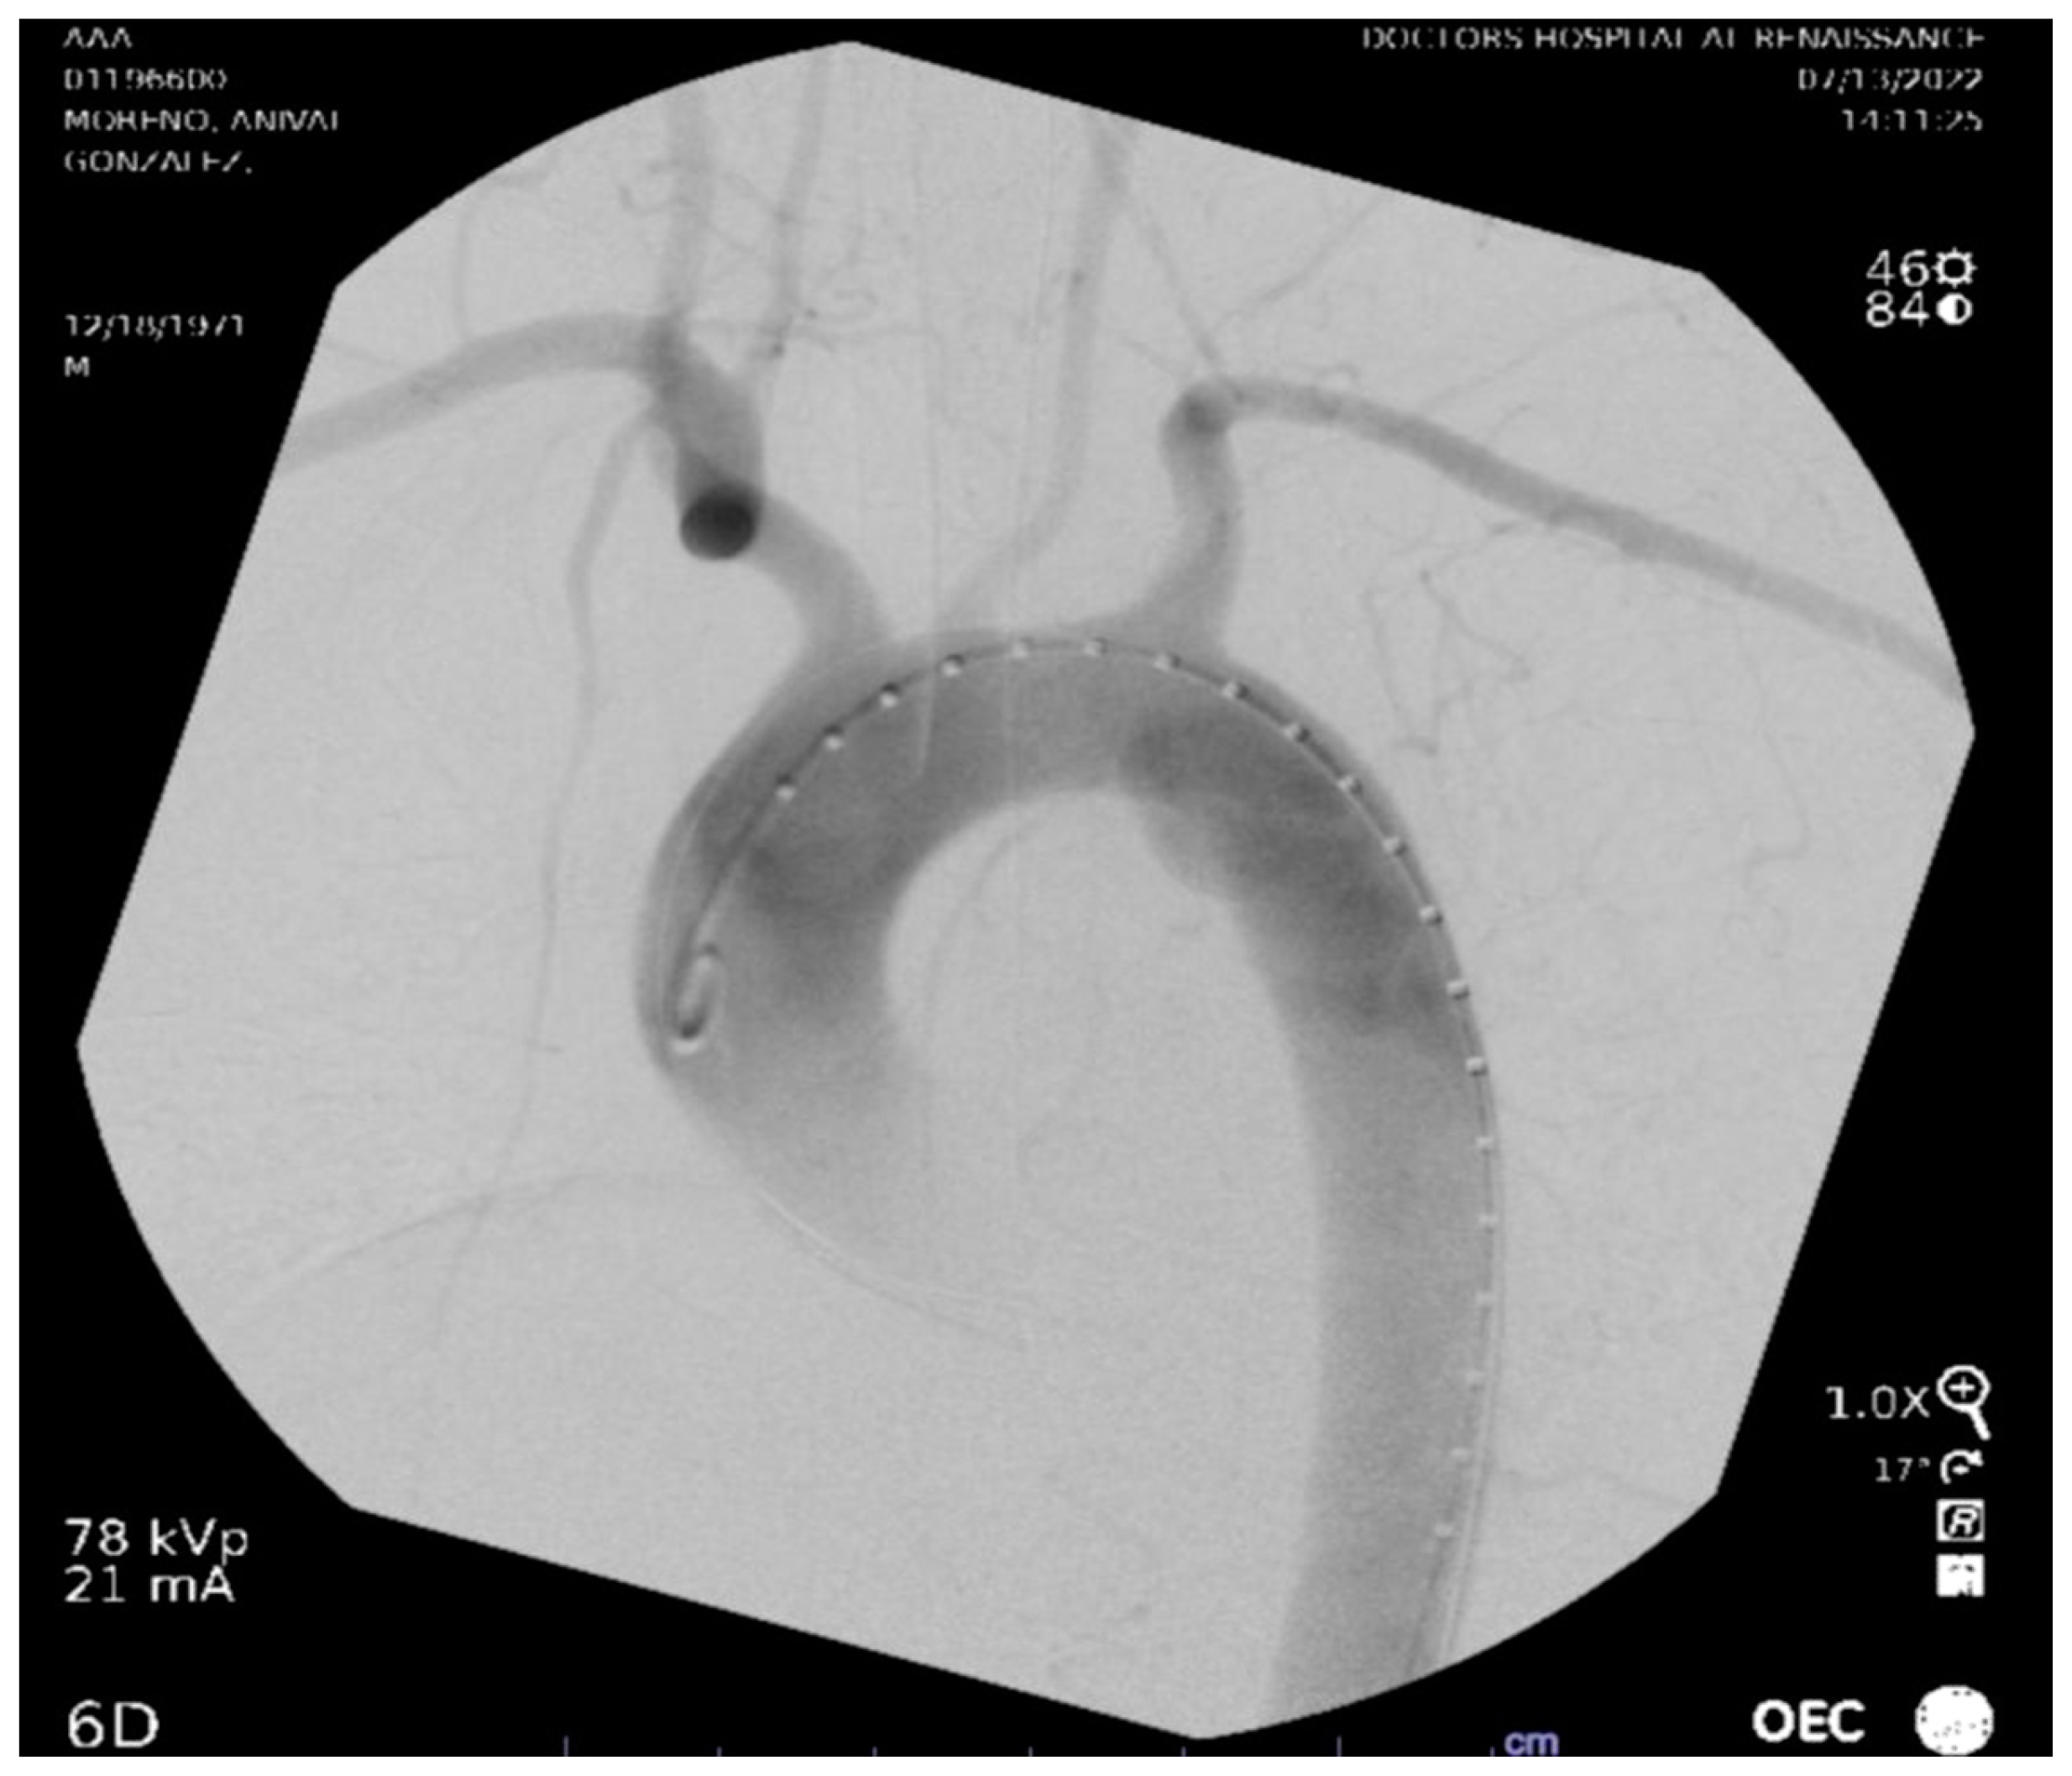

Figure 4. CT Angiography with contrast visualizing aortic arch and descending aorta preplacement of the stent.